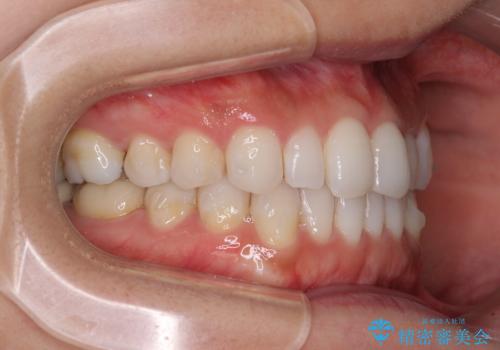

軽度の叢生をインビザライン・ライトで解消

- 前歯が気になるとのことで来院された患者様です。

歯列不正は軽微であったため、インビザライン・ライトにより、費用を抑えて矯正治療を行うこととしました。

短期間で気になる前歯の歯列を改善することができました。